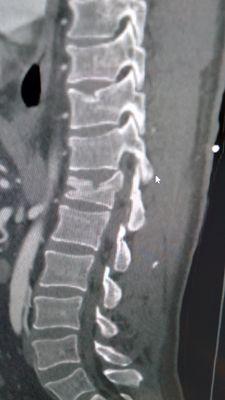

So first let me set up the back story. A few months back I had a seizure while riding in a vehicle and because of the seat belt I ended up breaking my own back. Burst fracture of my T-12...